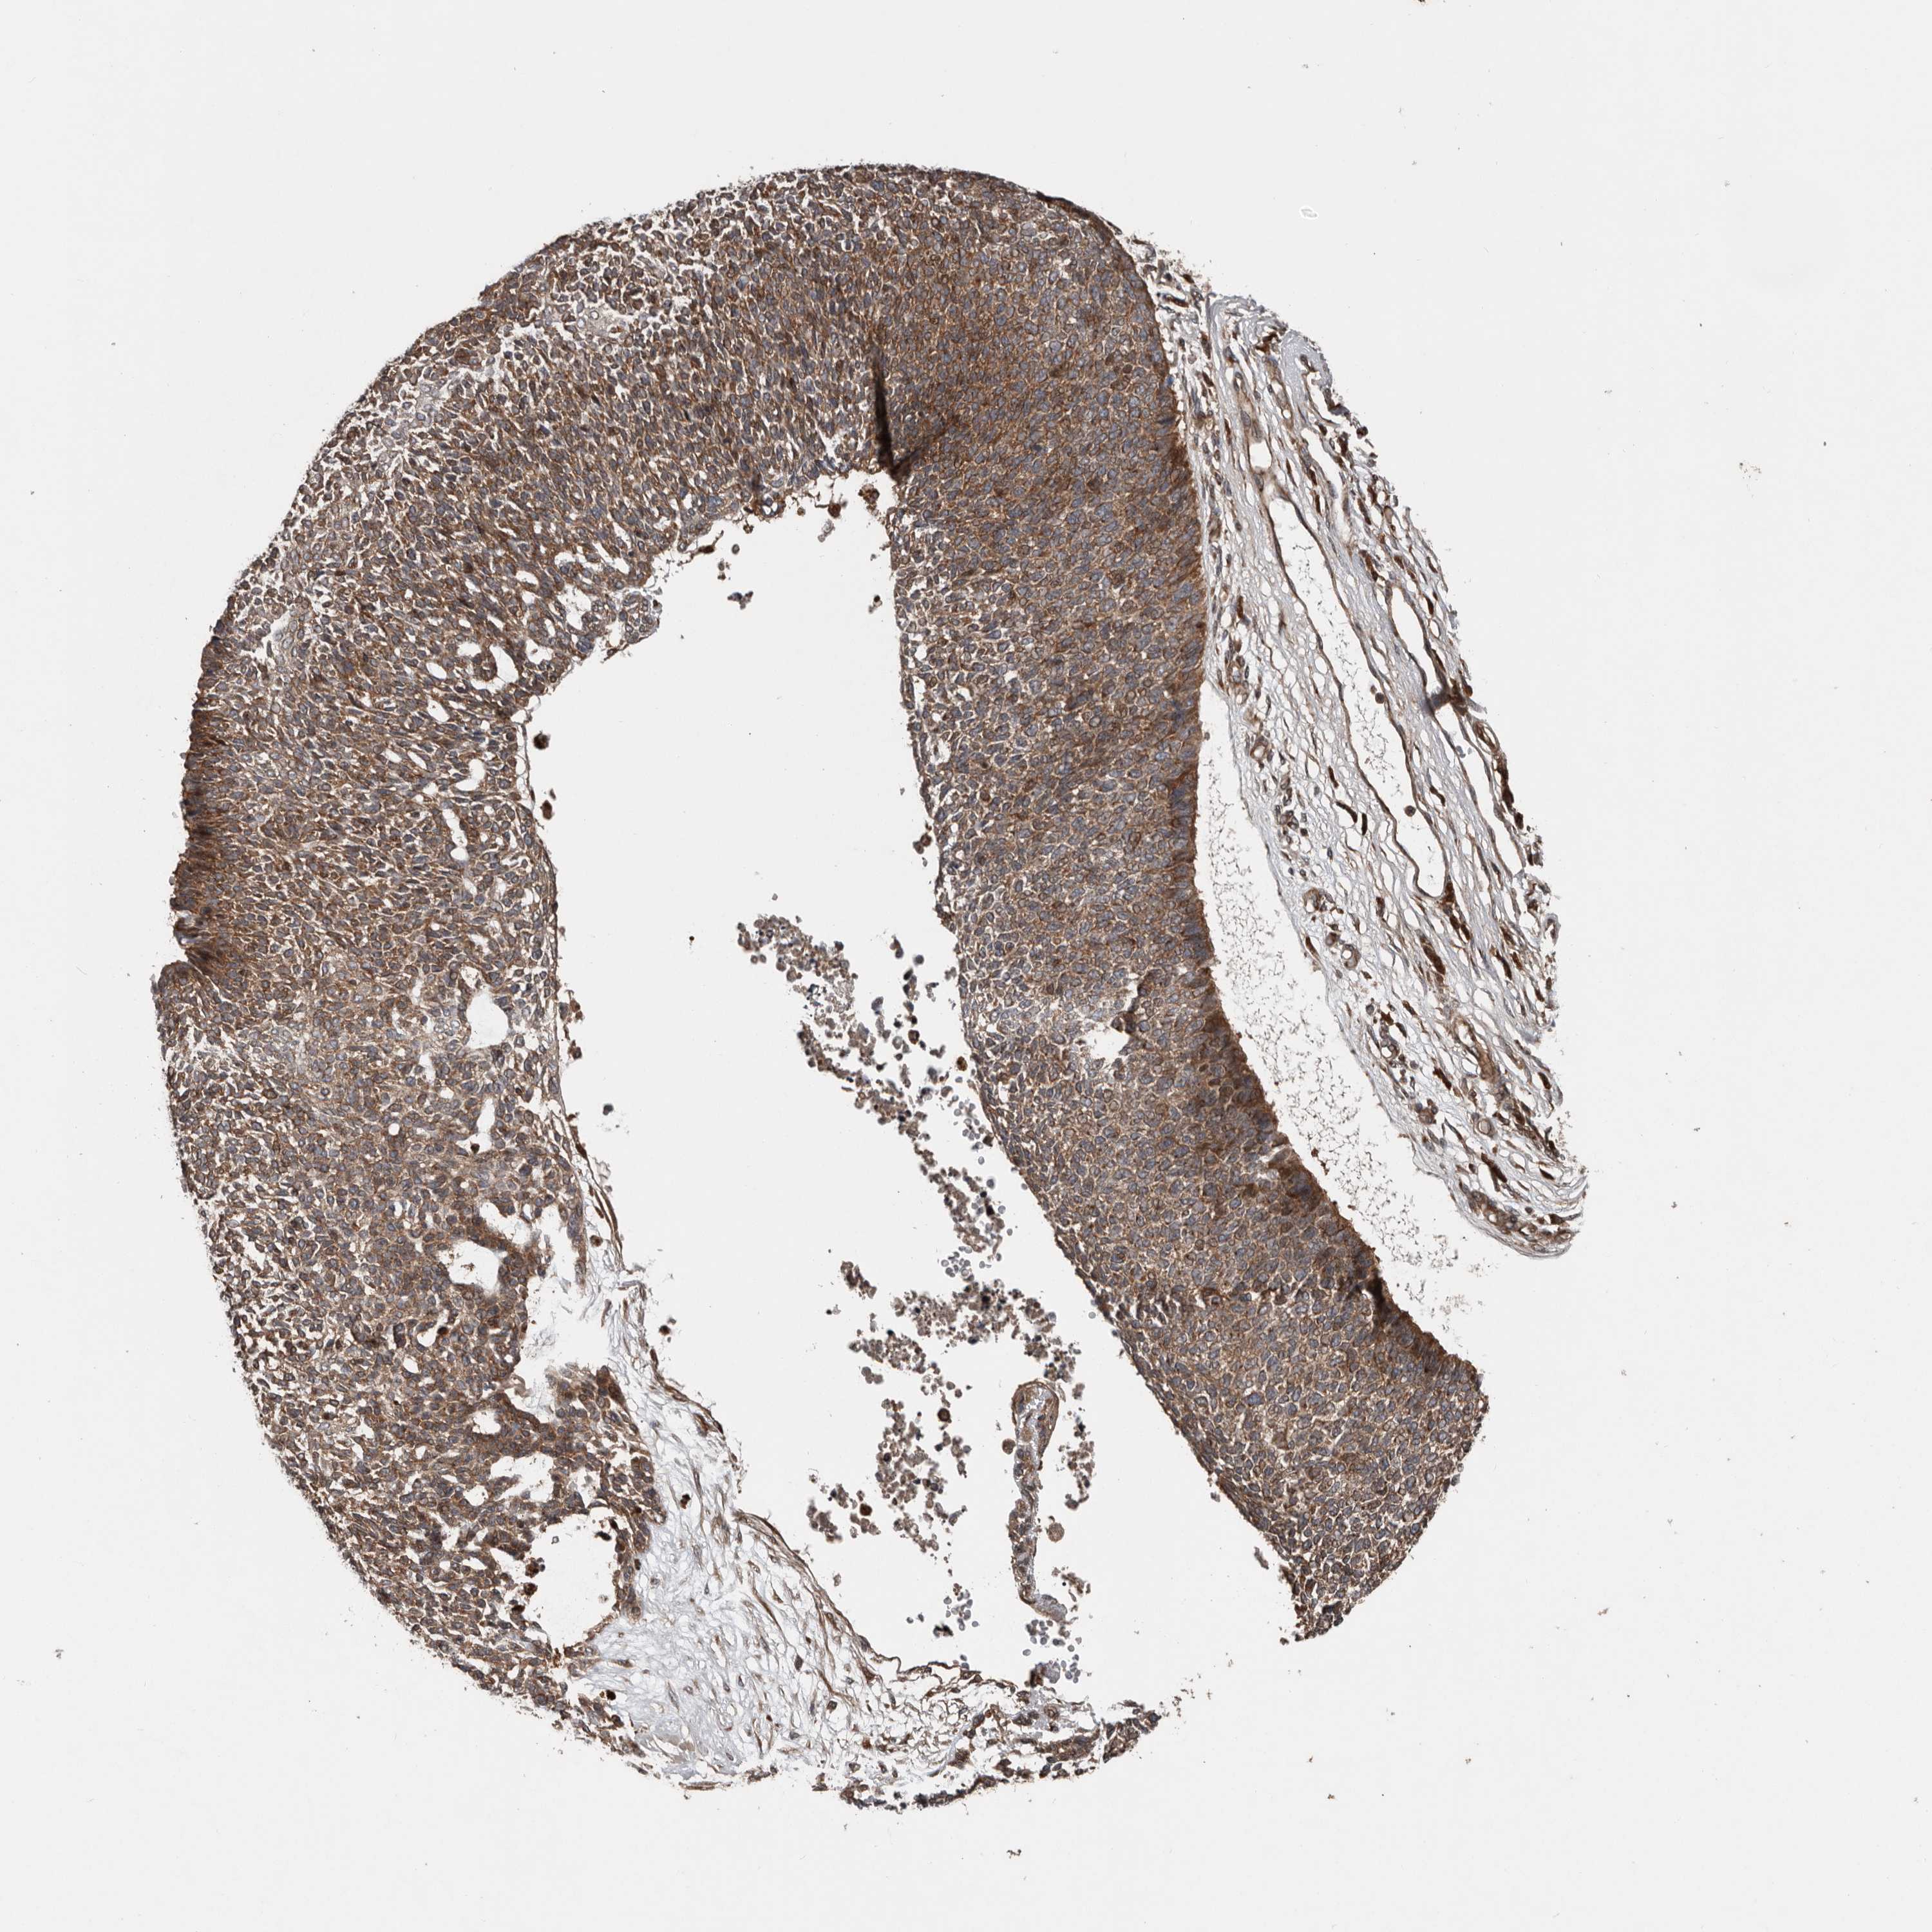

SKIN CANCER - Protein expressioni

A mouse-over function shows sample information and annotation data. Click on an image to view it in a full screen mode. Samples can be filtered based on level of antibody staining by selecting one or several of the following categories: high, medium, low and not detected. The assay and annotation is described here.

Each image is clickable and will lead to virtual microscopy that enables deeper exploration of all samples and also displays staining intensity scores, fraction scores and subcellular localization as well as patient and tissue information for each sample.

Antibody HPA028579

Basal cell carcinoma